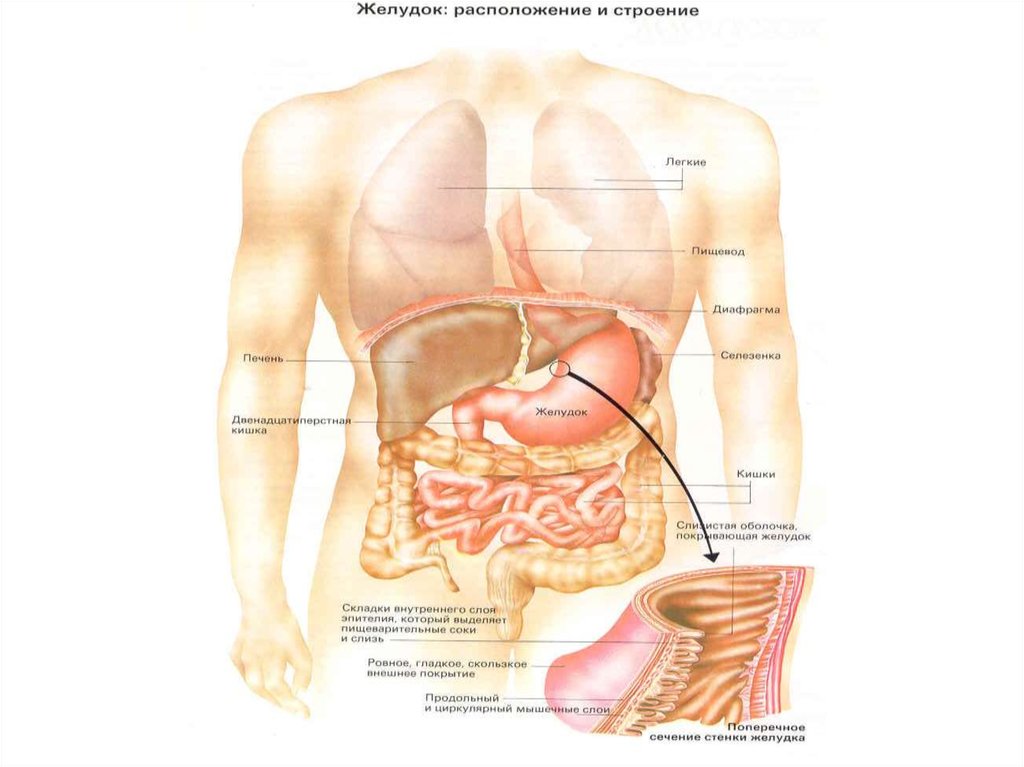

Анатомия желудка и сердца: визуализация и изучение

Раздел: Фотопанорама